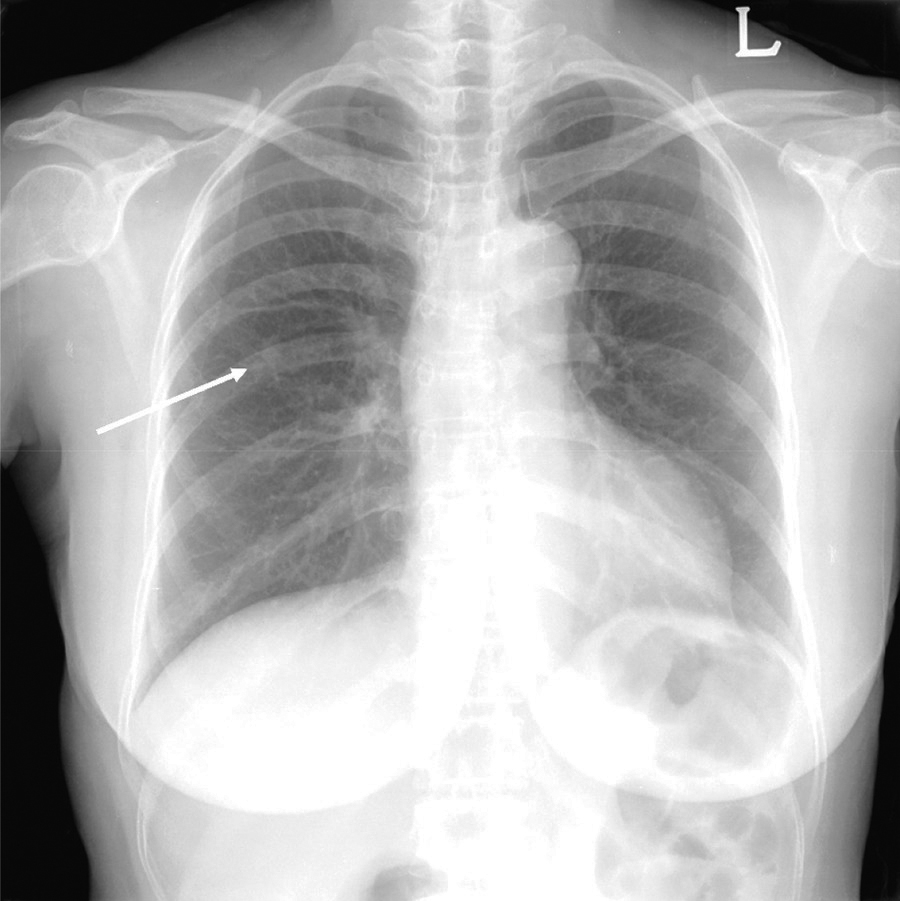

Figure 1

Initial chest radiograph shows an incidental nodule in the right upper lung field (arrow).